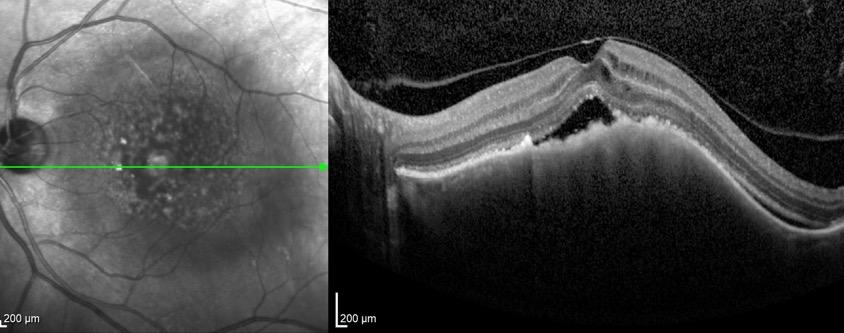

Type 1 MNV is characterized by the growth of vessels from the choriocapillaris into the subRPE space. On fluorescein angiography (FA), Type 1 MNV commonly presents late leakage of undetermined source, defined as areas of leakage at the level of the retinal pigment epithelium in the late phase of the angiogram without well-demarcated areas of hyperfluorescence in the early phase of the angiogram that would explain the leakage. It may also appear as fibrovascular pigment epithelial detachment, defined as areas of irregular retinal pigment epithelium elevation detectable on stereoscopic angiography. As a result, Type 1 MNV was originally termed occult neovascularization.3 Indocyanine green angiography (ICGA) should be used to visualize part of the vascular structure but it often reveals only late staining of the lesion, referred to as a plaque.4 (Figure 1)

1. Multimodal imaging of Type 1 macular neovascularization. Fundus autofluorescence (A) showing fine alteration of retinal pigment epithelium. Late phase (B) of fluorescein angiography revealing pinpoints of hyperfluorescence. Both early (C) and late phases (D) of indocyanine green angiography reveal a central hyperfluorescent zone, indicative of type 1 macular neovascularization, consistent with optical coherence tomography angiography (E). Optical coherence tomography displaying a shallow irregular elevation of retinal pigment epithelium (F).